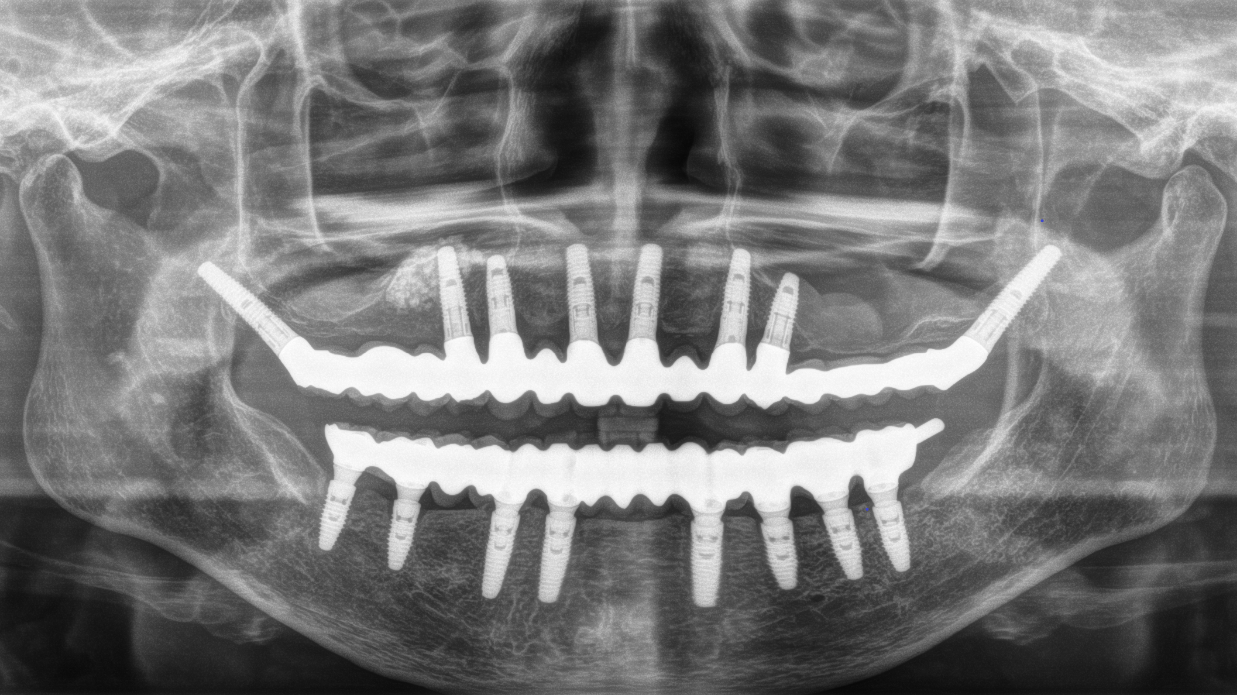

インプラント8本で14本の歯を並べたケース・仮歯代含む (函南町在住 女性

抜歯後、片顎8本のインプラントを埋入し、即日に仮歯を製作する事により、1日で片顎14本の歯を回復します。事前にインプラントを埋入する位置をCTによりシミュレーションし、埋入ガイド、仮歯を準備したうえで手術を行います。埋入ガイドにより、正確な位置にインプラントを埋入することができます。

完成後のレントゲン写真

最終的な被せ物を装着した状態のレントゲン写真。

(今回は下顎ですが、その前に上顎は治療済みです。)